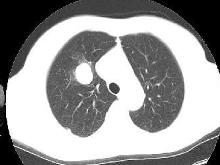

5、CT檢查可以較清楚地顯示病變的形態,還可確認異常動脈的存在。典型表現為:正常肺支氣管動脈和靜脈束遠離或圍繞在隔離肺葉外周,偶見鈣化。如與支氣管樹交通造成感染,其表現為含氣囊腫,有或無液平,周圍可見炎性浸潤,也可呈囊腫樣表現,可有氣液平。但診斷陽性率並不高。

根據病史、臨床表現,結合影像學檢查(主要為增強CT)可做出診斷。